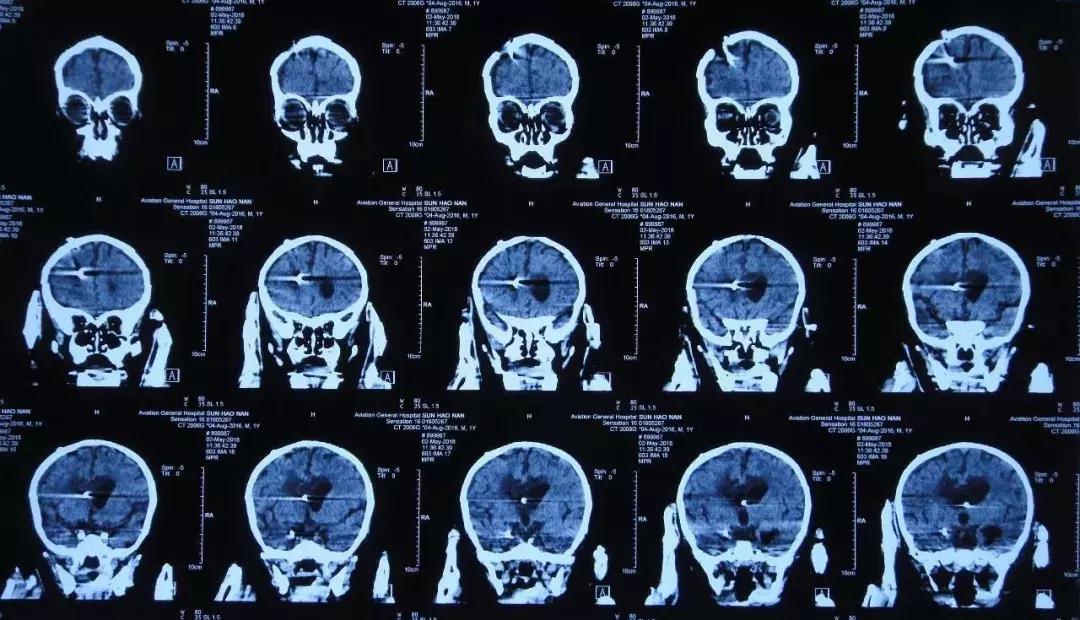

2018年3月14日头CT:脑室系统扩张 伴脑室旁水肿

2018年3月16日复查头CT:脑室系统扩张明显

3月14日,复查头CT:脑室系统扩张,伴脑室旁水肿, 3月15日再次加用两性霉素B,3月16日患儿呕吐明显,复查头CT:脑室系统扩张明显,当天晚上接受了经右额侧脑室穿刺Ommaya囊植入术,持续引*脑流**脊液,每日经右侧侧脑室腹壁外引流管引流量约60-80ml,Ommaya囊每日穿刺引流30ml,但是效果不佳,患儿仍有发热,呕吐等症状。为了寻求进一步治疗患儿转入李小勇脑脊液科。